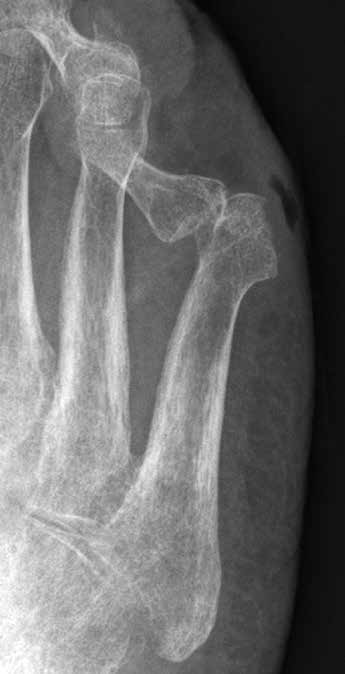

Ihre Domäne hat die Orthetik an den unteren Extremitäten bei der Wiederherstellung einer stabilen Belastbarkeit des Beines 15 16 17. Insbesondere bei Defiziten in der Dorsalextension des Fußes leisten Orthesen (meist Karbonfedern) gute Dienste. Bei der Versorgung des Patienten sollte aber berücksichtigt werden, dass in fast allen Fällen die Binnenmuskulatur des Fußes mit beeinträchtigt ist. Ohne ausreichende Stützung kommt es beim langfristigen Belasten des Fußes zum Einbrechen des Fußskelettes mit sekundären Druckschäden.